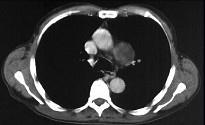

问题 男性,53岁,2年前被踢伤胸部,最近感胸部不适,常规胸片检查,示纵隔内病变,加扫CT平扫及增强,结果如图所示 ( )

选项 A、球形病灶外围见半月形低密度影,其内有斑片状高密度影,考虑为血栓形成 B、结合临床,考虑为主动脉假性动脉瘤(外伤性) C、CT增强扫描示主动脉弓层面左侧缘不规则,造影剂流入球形病灶内 D、结合临床,考虑为主动脉夹层 E、胸片示上纵隔见类圆形高密度影,以侧位片明显

答案 ABCE